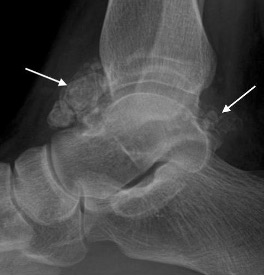

Synovial osteochondromatosis of the ankle joint with multiple intra-artcular ossific bodies (arrows)